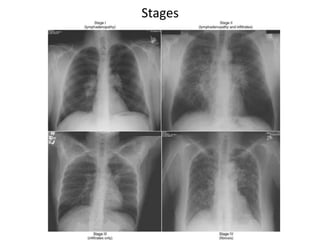

4 Stages of Pulmonary Sarcoidosis

I Bilateral hilar lymphadenopathy

and paratracheal adenopathy

55-90%

remission

II Mediastinal adenopathy with

pulmonary parenchymal

involvements

40-70%

III Pulmonary parenchymal without

adenopathy

10-20%

IV Pulmonary fibrosis with

honeycombing

0-5%

Stages

91 91